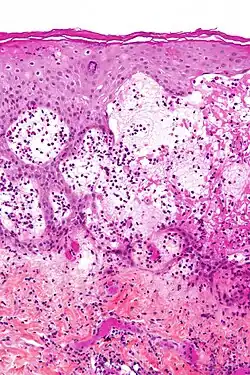

| Micrograph of gestational pemphigoid showing the characteristic subepidermal blisters and abundant eosinophils. HPS stain. | |